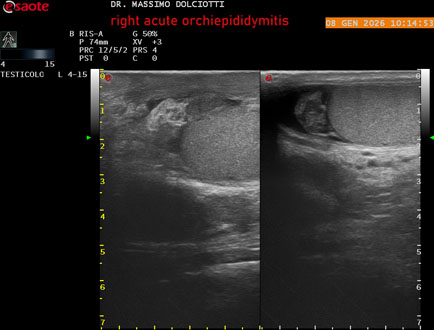

Data inserimento: 08/01/2026

Ecografia del: 08/01/2026

Strumento: Esaote MyLab Eight

Sonda: Lineare Multifrequenza 4-15 MHz

Età Paziente: M 74 anni

Motivazione dell'esame: da 3 giorni dolore e tumefazione al testicolo destro.

Commento all'esame: le immagini ed il video documentano il didimo destro, aumentato di volume, con incremento della vascolarizzazione; aumentato di volume e di vascolarizzazione anche l'epididimo destro, Normale il didimo sin e l'epididimo sinistro, Gli elementi ecografici segnalati orientano per orchiepididimite destra acuta.

Conclusioni: orchiepididimite destra acuta (right acute orchiepididymitis).

Presentazione: Dr. Massimo Dolciotti - Ancona

Elaborazione digitale: Andrea Dini - Ancona